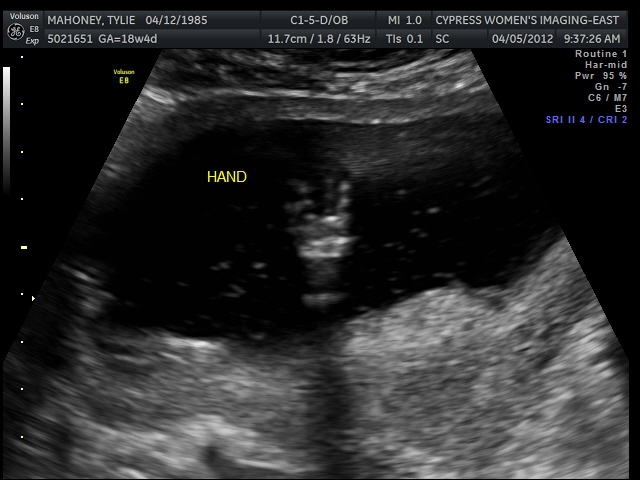

We had our sonogram this morning!!! WOOO!

Can I first just say...it really doesn't get old seeing your sweet baby. I could just be in that room all day watching the baby move around and get a glimpse of their secret little world!

So here is a pic of the baby's profile! ADORABLE!!!

Here is some of the hands...

Live long and prosper...hahaha!

Gave a thumbs up! What a character already!

I know you don't really care about the hands...you want a shot of the baby's gender...

Well we found out pretty quickly in the appt. I asked the lady to check a few more times to make sure we saw what we saw....

We saw a little Penis!!! LOL!!! I was SO surprised (which is why I had her check a few times). I was sure it was going to be a little girl. This little boy is a delight already. Can't believe we are almost halfway along in the pregnancy. It wont be too long before we meet this sweet little addition!

Yay for a BOY!!!!!